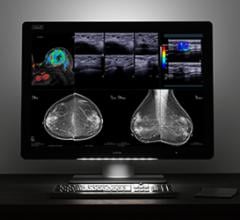

Mammography

Mammography is a breast imaging technique that uses X-rays to diagnose and locate tumors of the breasts.

May 24, 2017 — Barco announced that several of its diagnostic display systems will be on display at the 2017 Society for ...